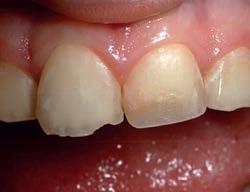

Before whitening.

After one month of whitening.

Moderate to advanced tetracycline stains. Improvement in 2 weeks. With tetracycline stains, treatment can require 2 to 6 months.1